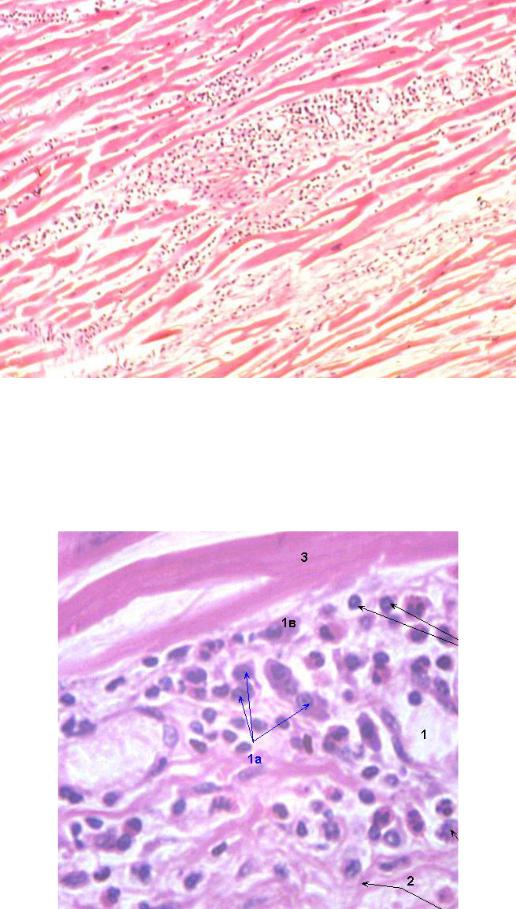

Межуточный миокардит: гистологические исследования